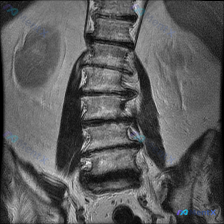

整理到一份腰椎冠状位MRI影像资料,先给大家看客观表现: - 脊柱力线:腰椎向右侧侧弯 - 椎体:高度、排列大致连续,无明显滑脱,骨质信号未见明确局灶异常 - 椎间盘:普遍T2低信号(脱水退变),下腰椎(L3/4-L5/S1)椎间隙变窄,冠状面见轻度周边膨隆 - 小关节:多节段骨质增生、间隙窄,呈退...